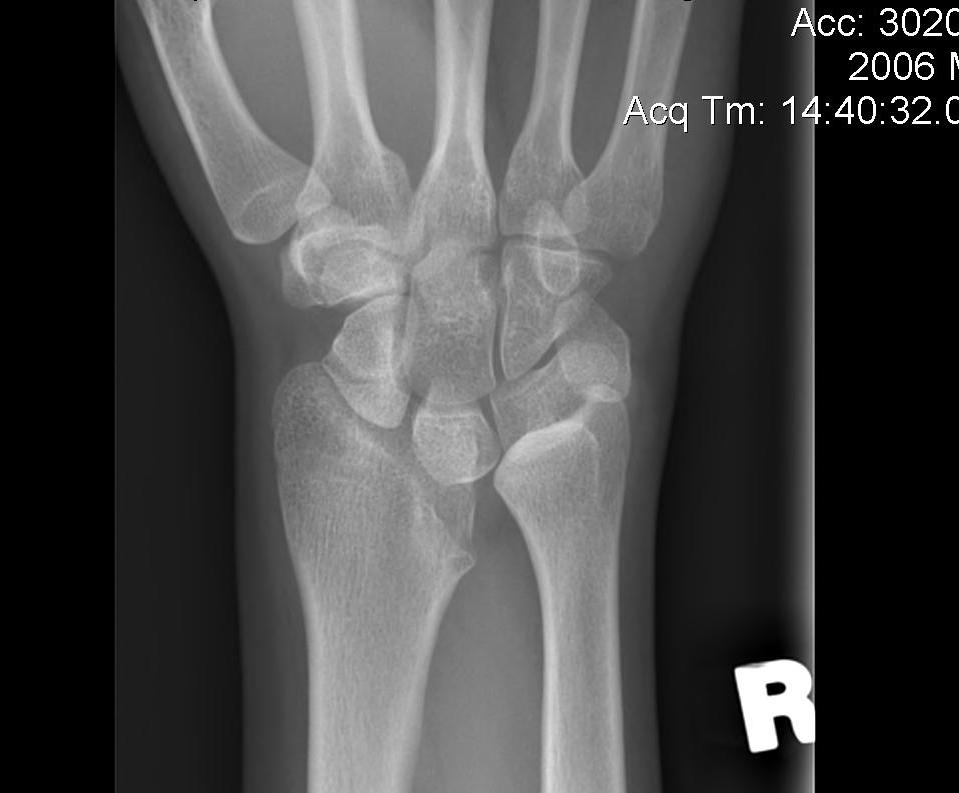

X-ray

Volar-ulna tilt of the distal radius with dorsal subluxation of ulna / distal radius triangular shape

Proximal carpal row becomes wedge shaped

- lunate "falls into" the radio-ulna gap

DRUJ widened